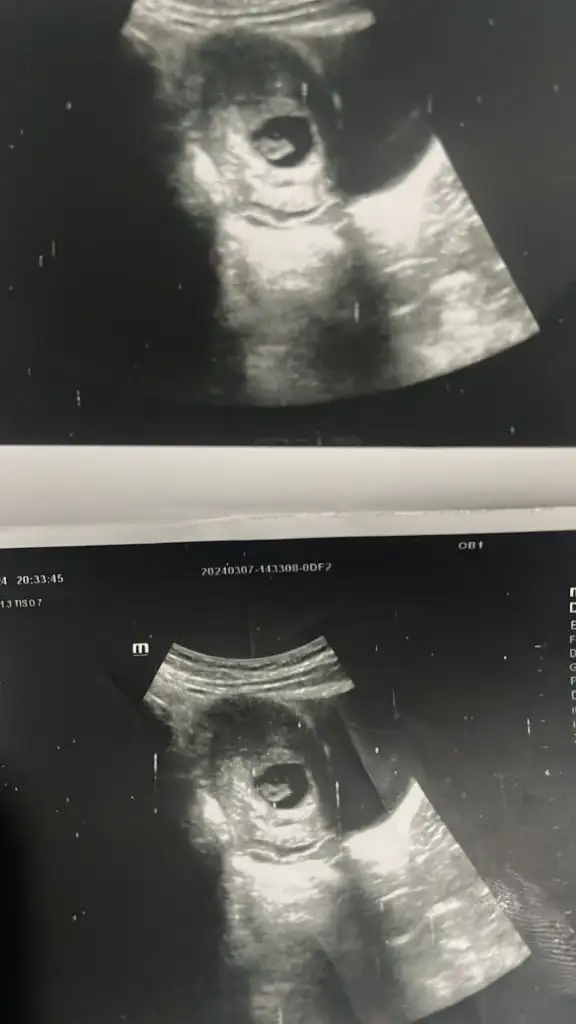

Lütfen benim ulturasonuma da bakarmısınız ?? Karnımdan bakıldı 10+6